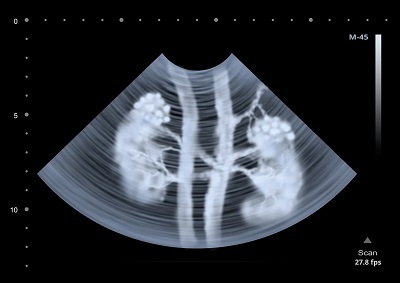

The team analyzed the brains of 52 decedents and found the individuals had higher concentrations of microplastics in the brain compared to the liver and kidneys.

Still, he said the group’s analysis suggests some microplastics aren’t remaining in the body indefinitely. Lower concentrations in the liver and kidneys indicate those organs are doing their jobs and working to clear plastic from our systems. But, plastics in the liver can be widespread.

Images of the plastics in those organs support that theory. However, the number of microplastics in the brain and liver increased within the past 20 years, samples from the decedents showed. Some of them had higher concentrations of plastic in the brain by as much as 50 percent.